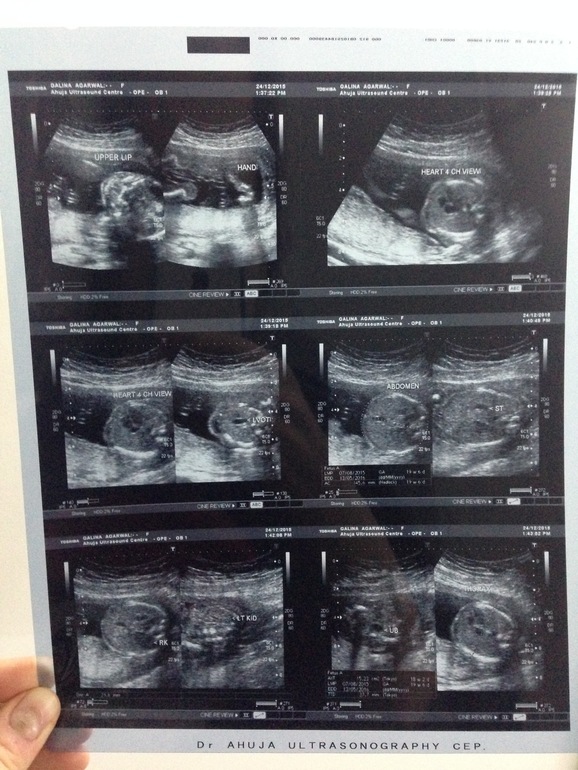

Приехали, вход в "клинику" выглядел как вход в развалины старого замка в Париже времён Куликовской битвы, я заменжевалась, на "ресепшене" не поняли, что мы хотим, потом вышел доктор и спас нас! Вот как такие специалисты работают в таких условиях??? Оборудование классное, доктор - душка, потратил на нас час, наверное, рассказывал про каждую часть тела малыша, терпеливо ждал, пока мы разглядим.

ВСЕ У НАС В ПОРЯДКЕ! Доктор замерил все параметры, какие надо было по моему подготовленному образцу. Потом он, конечно, перестарался в тот момент, когда мы попросили распечатать фотки. Доктор сказал: "Хорошо, придёте вечером за отчётом и фотками")) Мы пришли, открываем папку: а там фоток 100, всех частей тела и органов малыша во всех проекциях!:))) перестраховался)) вот на таких листах фото, штук 15 листов)) Забавно, что мне с ними делать! Моя любимая фотка - левая лапка и пяточка))) Такая милота....